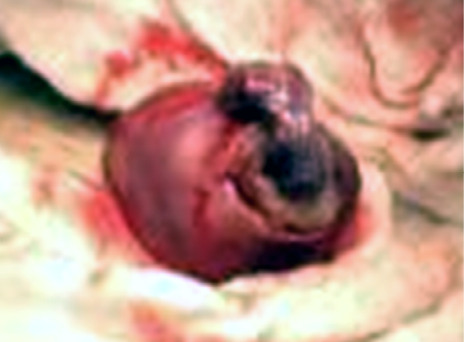

Paciente de 18 años, primípara, sin antecedentes patológicos de importancia. Sin uso de método anticonceptivo desde hace seis meses. La que consulta por cuadro clínico de 72 horas de evolución caracterizado por dolor cólico que progreso de leve a severo, localizado en hipogastrio, con metrorragia escasa. Ingresa por sus propios medios. Al examen físico Tensión Arterial de 108/69mmHg, Frecuencia Cardiaca de 81 por minuto, Frecuencia respiratoria de 18 por minuto y Temperatura 36,9ºC., abdomen doloroso a la palpación del flanco derecho, Signo de Blumberg (+), puño percusión (–) bilateral. Examen ginecológico: vagina eutrófica, cérvix sin alteraciones, útero en Anteversoflexión, leve aumento de tamaño, con dolor a la palpación de anexo derecho. Se solicitan paraclínicos: Hemograma: Glóbulos Rojos: 3960000/mm3, Glóbulos blancos: 10800/mm3, Hemoglobina: 12,6g/dl, Hematocrito: 36,9%; ß-hGC de 10.290 mUI/ml; Ecografía Transvaginal: endometrio engrosado y saco gestacional en cuerno derecho con feto vivo, de 9 semanas, con escaso líquido libre en el fondo de saco de Douglas. Se diagnostica: Embarazo ectópico cornual, y se procede a la realización de laparotomía exploratoria como en el caso anterior, confirmándose el diagnóstico (Figura 2). La paciente evolucionó de forma satisfactoria y abandonó la clínica a las 18 horas de la intervención en óptimas condiciones.

Figura%2013-2.jpg

Figura 2. Fotografía del ectópico en el intraoperatorio.